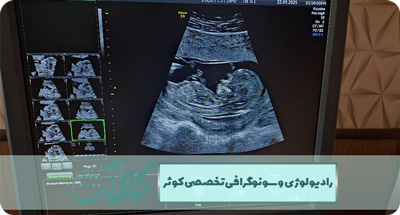

گامی مطمئن برای سلامت مادر و جنین

دوران بارداری، دورهای پر از سوال و نگرانی برای مادران است. سونوگرافی بارداری، یکی از دقیقترین روشها برای بررسی وضعیت جنین و اطمینان از سلامت اوست. با سونوگرافی، پزشک میتواند رشد طبیعی جنین را ارزیابی کند و هرگونه مشکل احتمالی را زودتر شناسایی کند.

در میانهی مسیر شگفتانگیز بارداری، جایی میان نگرانیها و رویاها، سونوگرافی آنومالی اسکن همچون نوری روشن در دل تاریکیهای نادیده، آرامش را به قلب مادران هدیه میدهد.

این اسکن، صرفاً یک تصویر پزشکی نیست؛ روایتی از رشد زندگی است، داستانی از سلامت و تعادل.

بارداری یکی از زیباترین و در عین حال حساسترین دورانهای زندگی یک زن است. در این مسیر، هر تصمیم آگاهانه میتواند سرنوشت آیندهای روشنتر را رقم بزند. غربالگری بارداری، گامی کلیدی در این سفر است؛ گامی که با بررسی دقیق سلامت جنین، مادر را از اضطرابهای بیپاسخ رها میکند و فرصتی طلایی برای پیشگیری بهموقع ایجاد میکند.